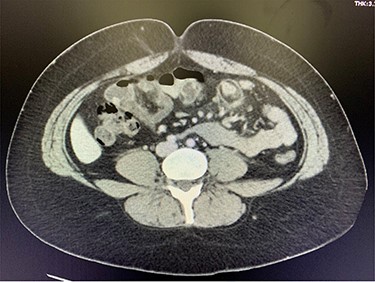

A 29-year-old female presented to the emergency room after several days of worsening epigastric and RUQ abdominal pain, nausea and loss of appetite. On examination, her abdomen had mild tenderness to palpation in the epigastric region and no tenderness in the RLQ. Murphy’s sign was negative. Vital signs were all within normal limits, and the remainder of her physical exam was unremarkable. White blood cell count was elevated, and CT was consistent with small bowel intussusception and inflammatory changes at the mesentery (Fig. 1). The patient was admitted to the hospital for one night, where she was observed. Her pain and nausea did not improve. The decision was made to proceed with surgery.

CT consistent with small bowel intussusception and inflammatory changes at the mesentery.